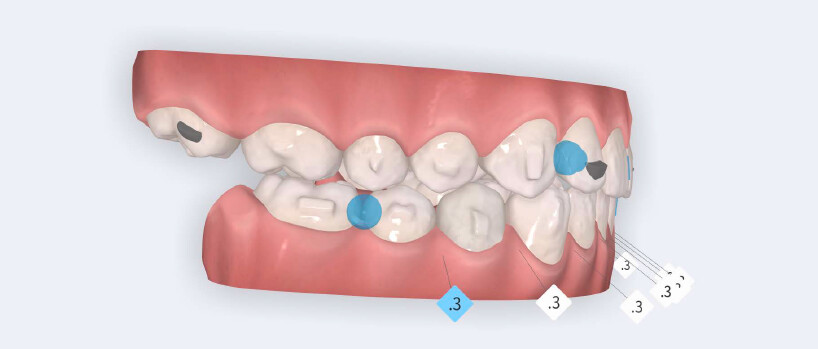

- Initiation of mandibular advancement from the 4th aligner using mandibular advancement blocks;

- Arch expansion to resolve crowding and improve transverse coordination;

- Selective interproximal reduction in the mandibular anterior region to create space and control incisor inclination;

- Programmed intrusion of the maxillary central incisors to reduce the gingival display and correct the gummy smile;

- Intrusion of mandibular incisors and canines to level the Curve of Spee;

- Use of Class II elastics on Angel Buttons during the refinement phase to reinforce sagittal mechanics, introduced during the additional aligners stage.

The treatment was carried out using Angel Aligner clear aligners, with strict adherence to periodontal biological limits. Both maxillary incisor intrusion and transverse expansion were carefully monitored throughout the process to prevent any periodontal compromise. Mandibular advancement was initiated directly from the 4th aligner using advancement blocks, eliminating the need for a preliminary pre-advancement phase. The patient was at the CS3 stage of cervical vertebral maturation, corresponding to the pubertal growth spurt, a biologically favorable period for condylar remodeling and skeletal adaptation. A total of 35 aligners with advancement blocks were used, followed by 10 additional aligners incorporating Class II elastics on Angel Buttons to finalize rotations and alignment. With weekly aligner changes, the overall treatment duration was approximately 45 weeks (10 months), aligning with the expected biological timeline for condylar remodeling. For mandibular anterior intrusion, the Frog Protocol combined with interproximal reduction (IPR) achieved complete leveling of the Curve of Spee.